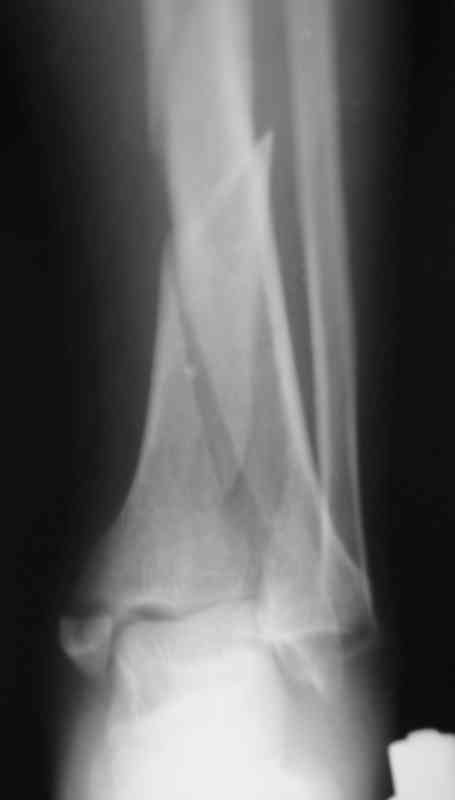

Судя по снимкам (спиральный перелом диафиза продолжающийся до сустава, отрывной перелом внутренней лодыжки) механизм перелома - скручивание. Стоит сделать снимок на всю голень включая коленный сустав и поискать проксимальный перелом м.берцовой кости. Такие переломы сопровождаются разрывом межкостной мембраны и поэтому нестабильны, повреждение м.т.

значительное и как правило большие гематомы.

Внутрисуставной перелом простой - линейный, по этому не должно быть проблем с закрытой репозицией на ЭОПе. По моему мнению самый подходящий метод -